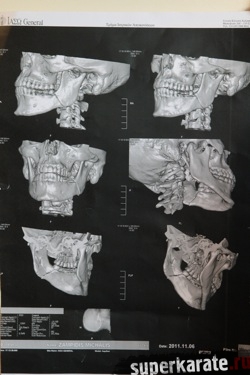

Обследование, проведенное в одной из лучших клиник города Афины квалифицированными греческими специалистами, прошло при участии официальных представителей Майка Замбидиса, мировой версии W5 и Московского общества греков. В рамках обследования Майку Замбидису был сделан рентгеновский снимок черепа, после чего снимок был подвергнут тщательному изучению. Также была проведен визуальный осмотр полученной травмы.

В результате полученных данных был сделан однозначный вывод о том, что Майк Замбидис действительно получил перелом нижней челюсти с левой стороны, и что дальнейшее продолжение боя могло привести к серьезным последствиям для здоровья Замбидиса.